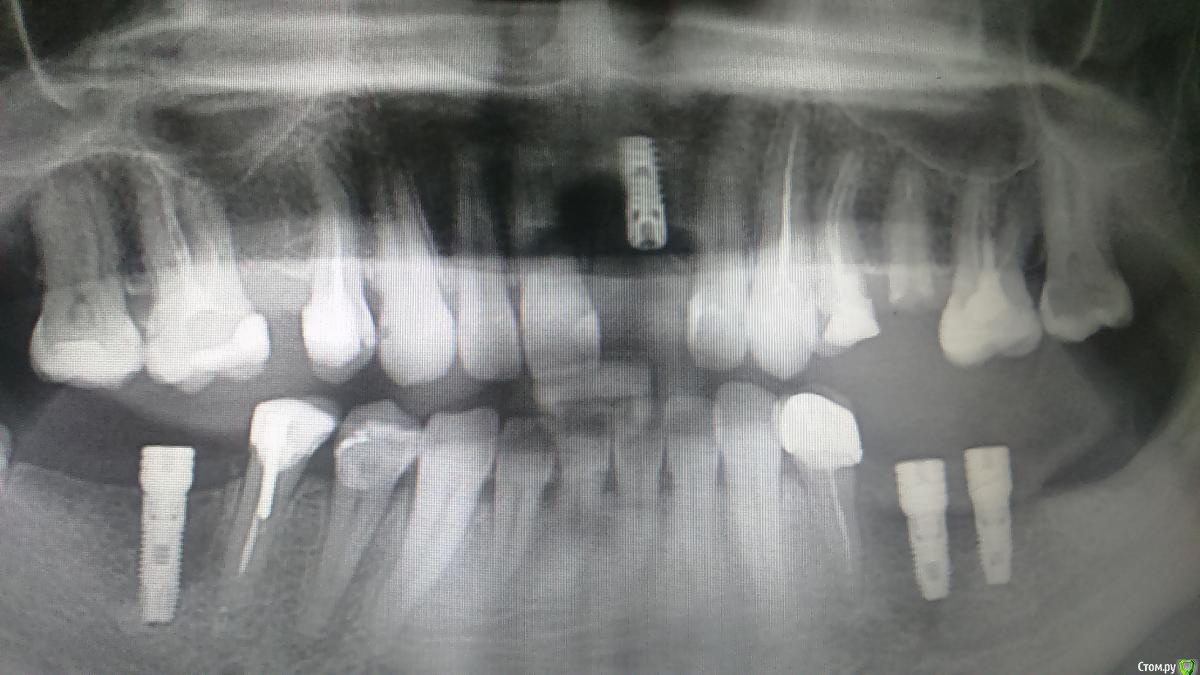

Platon Опубликовано 31 января, 2016 Автор Поделиться Опубликовано 31 января, 2016 Продолжение.не судите строго за фото, первый раз вообще фоткаю операцию)спасибо за советы.По порядку. После того, что мне написали, я решил все -таки уговорить на конусный имплантат (3.7-11.5 ImplantDirect). Также ортопед не хотел делать временную коронку, сказал что сделает каппу, птичку в топку -тоже сделали. Слизистая в области 21 была в рубцах. Исходя из этого всего я решил, коль временной коронки не будет, то сст подсаживать тоже не стану пока,(ортопеда уговаривал сделать временную коронку)))- торк был хороший 35-50н) для того чтобы сст попрактиковаться, но(((.в итоге, анестезия, разрез, сверло пилотное и сверло 2.2, далее расщепление с помощью набора майзенгер с использованием спредеров до нужного диаметра, установил имплантат, торк контролируемый, можно было подобрать любой) в итоге оставил 35. заглушка, совсем немного ксено, мембрана, ушился. ждем. Будет что-то типо каппы которая слегка отдавливает десну,формируя сосочки. не знаю, ни разу такую еще не видел.планирую на этапе раскрытия все-таки сст и временную коронку увидеть.вот. через 4 мес. выложу, что получилось) Если есть советы, критика, всему буду рад, спасибо 3 Ссылка на комментарий

St_Klaus Опубликовано 1 февраля, 2016 Поделиться Опубликовано 1 февраля, 2016 взять 11,5 не заглублять данный имплант, оставить 1,5 мм супракрестально., если позволяет десна, чтобы уменьшить ремоделинг кости. Соглашусь, альфа не предназначена для заглубления, если не ошибаюсь, даже производители не рекомендуют.Если есть советы, критика, всему буду рад, спасибоВсе хорошо, только чуть более небно бы вывел платформу, хотя бы 0,5 мм Ссылка на комментарий